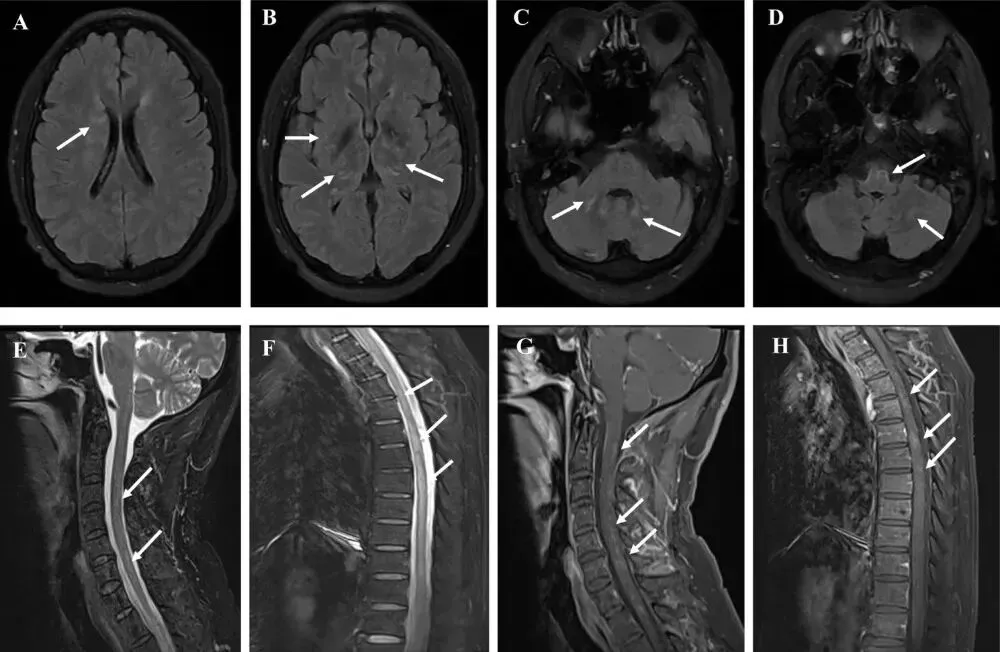

脑MRI显示T2/FLAIR高信号占67%(8/12),常见于脑干(n=5)、白质(n=4)、丘脑(n=3)和基底节(n=2)。4例影像正常。增强扫描3例软脑膜强化,未见典型脑室旁放射状强化(PVRL)。脊髓MRI(11例)异常占73%,长节段横贯性脊髓炎(LETM)占27%。颈、胸、腰段受累比例分别为64%、45%、18%。图2展示了代表性MRI图像(白质、基底节、脑干及脊髓病变),具体数据见表2。

图2 GFAP-A合并EBV阳性患者的MRI特征